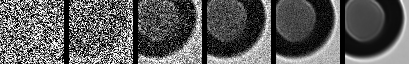

Image Generation. The image generation process begins with a sample of pure random Gaussian noise, denoted as . The goal is to progressively reverse the noising process, step by step, using the learned model to generate a realistic image. As shown in Figure 2, the model applies the learned denoising process starting from the random noise, iteratively refining the noisy image at each step to reconstruct the original data distribution.

At each step , the model predicts the denoised data from the noisy data by sampling from the learned distribution , as defined in the reverse process. This process continues until , at which point the generated data is a sample from the target distribution, resembling a clean image. The final result is an image that was generated from random noise, having gone through a series of denoising steps, guided by the reverse diffusion process learned during training.

Figure 2 provides a visualization of the denoising process in the reverse diffusion trajectory. Starting from pure Gaussian noise, the model progressively refines the image over 1,000 steps in our setup, gradually introducing particle-specific structures in a visually interpretable manner. To illustrate this process, we present six representative images along the trajectory. This progression highlights the ability of the generative model to recover subtle class-specific features, such as the halo effect in air bubbles or the smooth texture in silicone oil droplets, reinforcing confidence in the utility of these samples for downstream classification.